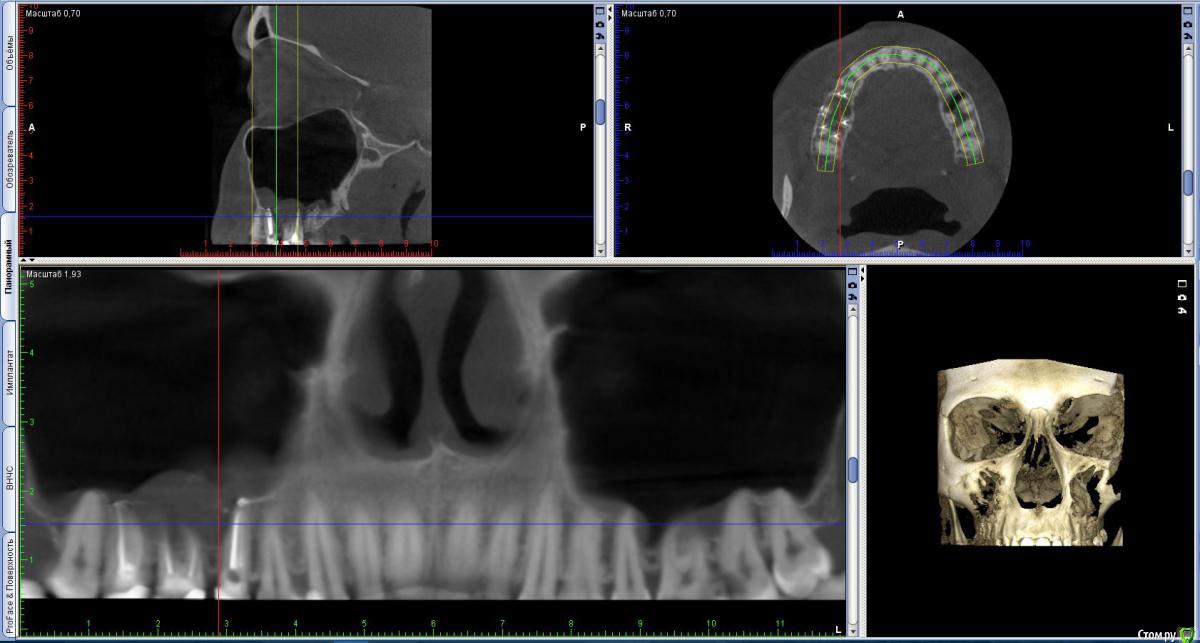

vicTORYa Опубликовано 6 октября, 2016 Автор Поделиться Опубликовано 6 октября, 2016 (изменено) Здравствуйте. Сделала КТ зубное, на 5 нижем правом зубе показалось что есть пятно странное. Подскажите не киста ли это? http://s016.radikal.ru/i337/1610/c3/a4db31326fc5.jpg Изменено 6 октября, 2016 пользователем vicTORYa Ссылка на комментарий

IvanK Опубликовано 10 октября, 2016 Поделиться Опубликовано 10 октября, 2016 выложите срез крупнее.. Ссылка на комментарий

vicTORYa Опубликовано 11 октября, 2016 Автор Поделиться Опубликовано 11 октября, 2016 https://drive.google.com/file/d/0B3wf-3dOFPYJUlVWUEs1WkRvQm8/view?usp=sharingсылка на срез но качесво самого КТ не очень хорошее, не знаю если это можоетможет выложить само КТ? Ссылка на комментарий

IvanK Опубликовано 12 октября, 2016 Поделиться Опубликовано 12 октября, 2016 не каждый имеет возможность и желание скачивать кт полностью в идеале - выложить скриншоты покрупнее Ссылка на комментарий

vicTORYa Опубликовано 12 октября, 2016 Автор Поделиться Опубликовано 12 октября, 2016 http://s018.radikal.ru/i513/1610/66/8dc851a309fdt.jpg http://s017.radikal.ru/i442/1610/bf/91e67d17fb96t.jpg http://s020.radikal.ru/i714/1610/00/bc65a4f99070t.jpg http://s017.radikal.ru/i438/1610/e9/60b8a7c730e7t.jpg http://s019.radikal.ru/i611/1610/71/877abc612cbet.jpg http://s020.radikal.ru/i713/1610/cf/c3fea13f9275t.jpg http://i013.radikal.ru/1610/e4/4b10087edaf6t.jpg http://s56.radikal.ru/i154/1610/b1/ac995a59f864t.jpg http://s017.radikal.ru/i440/1610/44/09882ae1e715t.jpg http://s017.radikal.ru/i407/1610/6d/be2fa1c9dde1t.jpg http://s019.radikal.ru/i617/1610/04/455b1edc56b6t.jpg http://s020.radikal.ru/i718/1610/0d/3d2250b2b1a2t.jpg http://s020.radikal.ru/i722/1610/00/3207bd86e2fdt.jpg http://s019.radikal.ru/i635/1610/40/bb734572883ct.jpg http://s017.radikal.ru/i413/1610/56/6e38ec905120t.jpg http://s011.radikal.ru/i318/1610/ca/3f09a02eb2f9t.jpg http://s017.radikal.ru/i429/1610/55/d0b2a1e679dat.jpg http://s016.radikal.ru/i334/1610/49/55e86166b9fdt.jpg http://s020.radikal.ru/i704/1610/c7/12ac17b8751dt.jpg http://s019.radikal.ru/i617/1610/8b/0c40b4ebd10ft.jpg http://s020.radikal.ru/i719/1610/66/d85d7d230523t.jpg http://s017.radikal.ru/i443/1610/20/f6c7e196559at.jpg Ссылка на комментарий

vicTORYa Опубликовано 23 октября, 2016 Автор Поделиться Опубликовано 23 октября, 2016 Скажите пожалуйста понятно ли что-то на этом КТ?С момента их лечения прошло чуть больше года, ждала не ставила коронки посмотреть не дадут ли проблемы зубы, в которых выведен материал, можно ли на данный момент сделать какие-то выводы? 6 и 7 не беспокоят, а вот 5 немного побаливает иногда. Просто иду на следующей неделе ставить коронки, всё ли в порядке с зубами, можно ли ставить коронки? Перелечивать так на всякий случаи не хочется, а только если там возникнет проблема. У мужа тоже есть один зуб с выведенным материалом и ему уже больше 10 лет и нет с ним проблем. Вот и думаю перелечивать только в случае необходимости.Сделать новый ренген не могу очень много уже сделал ренгенов за этот год. Ссылка на комментарий